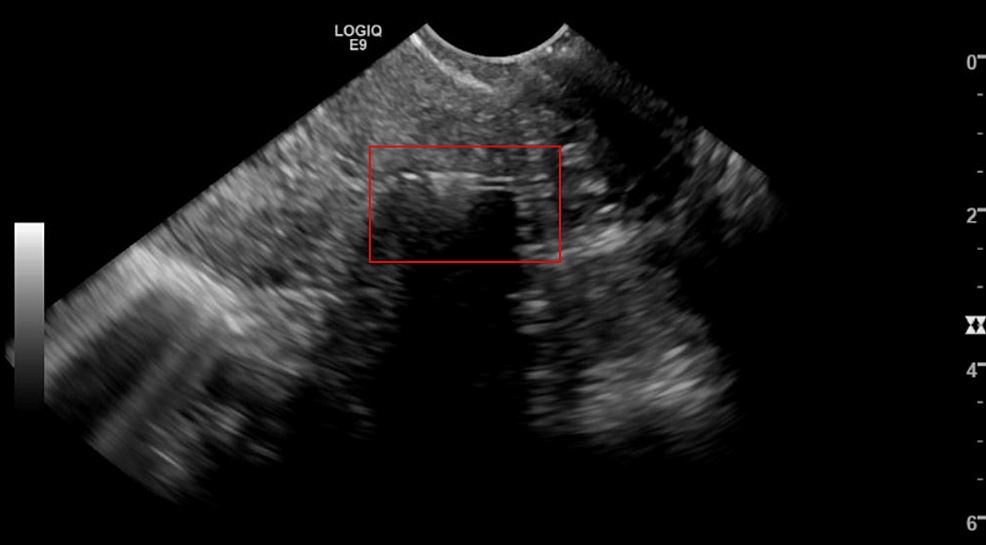

Ultrasound image of a malpositioned copper IUD. (A) 2D image; (B) 3D Copper Iud Ultrasound Today, two iuds are approved for use in the united states: The copper iud works by preventing sperm motility and viability within the uterine cavity by causing a localized cytotoxic inflammatory response. Because of this mechanism, copper iuds are. The copper iud (paragard) contains no hormones and prevents pregnancy for up to 10 years. Here we present two patients in. Copper Iud Ultrasound.